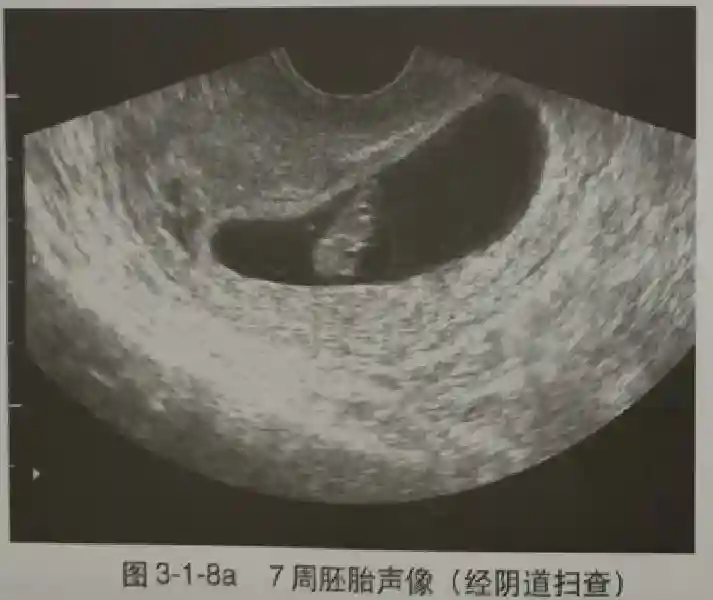

3??胚胎:胚胎通常在6-7周時(shí)可以為超聲顯示,起初為胎芽,表現(xiàn)為卵黃囊一側(cè)局部組織增厚,達(dá)到1 -2 mm 時(shí)才有可能為超聲測(cè)量出來(lái)。達(dá)4-5mm時(shí)可見(jiàn)胎心搏動(dòng),相應(yīng)孕周為6-6.5周,妊娠囊大小為13-18mm。胚芽長(zhǎng)度≥7㎜時(shí)仍未見(jiàn)心管搏動(dòng),提示胚胎停止發(fā)育。胚胎的出現(xiàn)和妊娠囊直徑的關(guān)系:妊娠囊直徑> 16 mm 時(shí),經(jīng)陰道超聲應(yīng)顯示胚胎。妊娠囊直徑> 25 mm 時(shí),經(jīng)腹超聲均應(yīng)顯示胚胎。

5??羊膜:早孕期羊膜囊菲薄,超聲常不能顯示。孕7周以后加大增益或者用高頻超聲可以顯示羊膜。羊膜囊位于絨毛膜內(nèi),胚胎位于羊膜囊內(nèi)。隨著胚胎增長(zhǎng),羊水增多,羊膜囊增大,孕12-16周時(shí),羊膜與絨毛膜全部融合,胚外體腔消失。宮腔線(xiàn)一側(cè)內(nèi)膜內(nèi)一圓形增強(qiáng)回聲區(qū),中央有小囊狀液性暗區(qū),宮腔線(xiàn)局部突起變形,稱(chēng)蛻膜內(nèi)征,用于判斷早早孕。